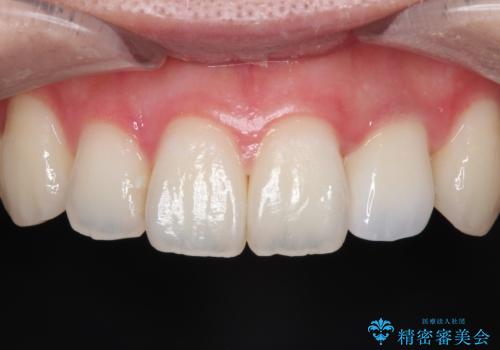

【セラミックインレー】虫歯になった詰め物部分を修復

- 前医で治療された詰め物の部分に、定期検診で虫歯が見つかったため、セラミックインレーにて修復治療を行いました。